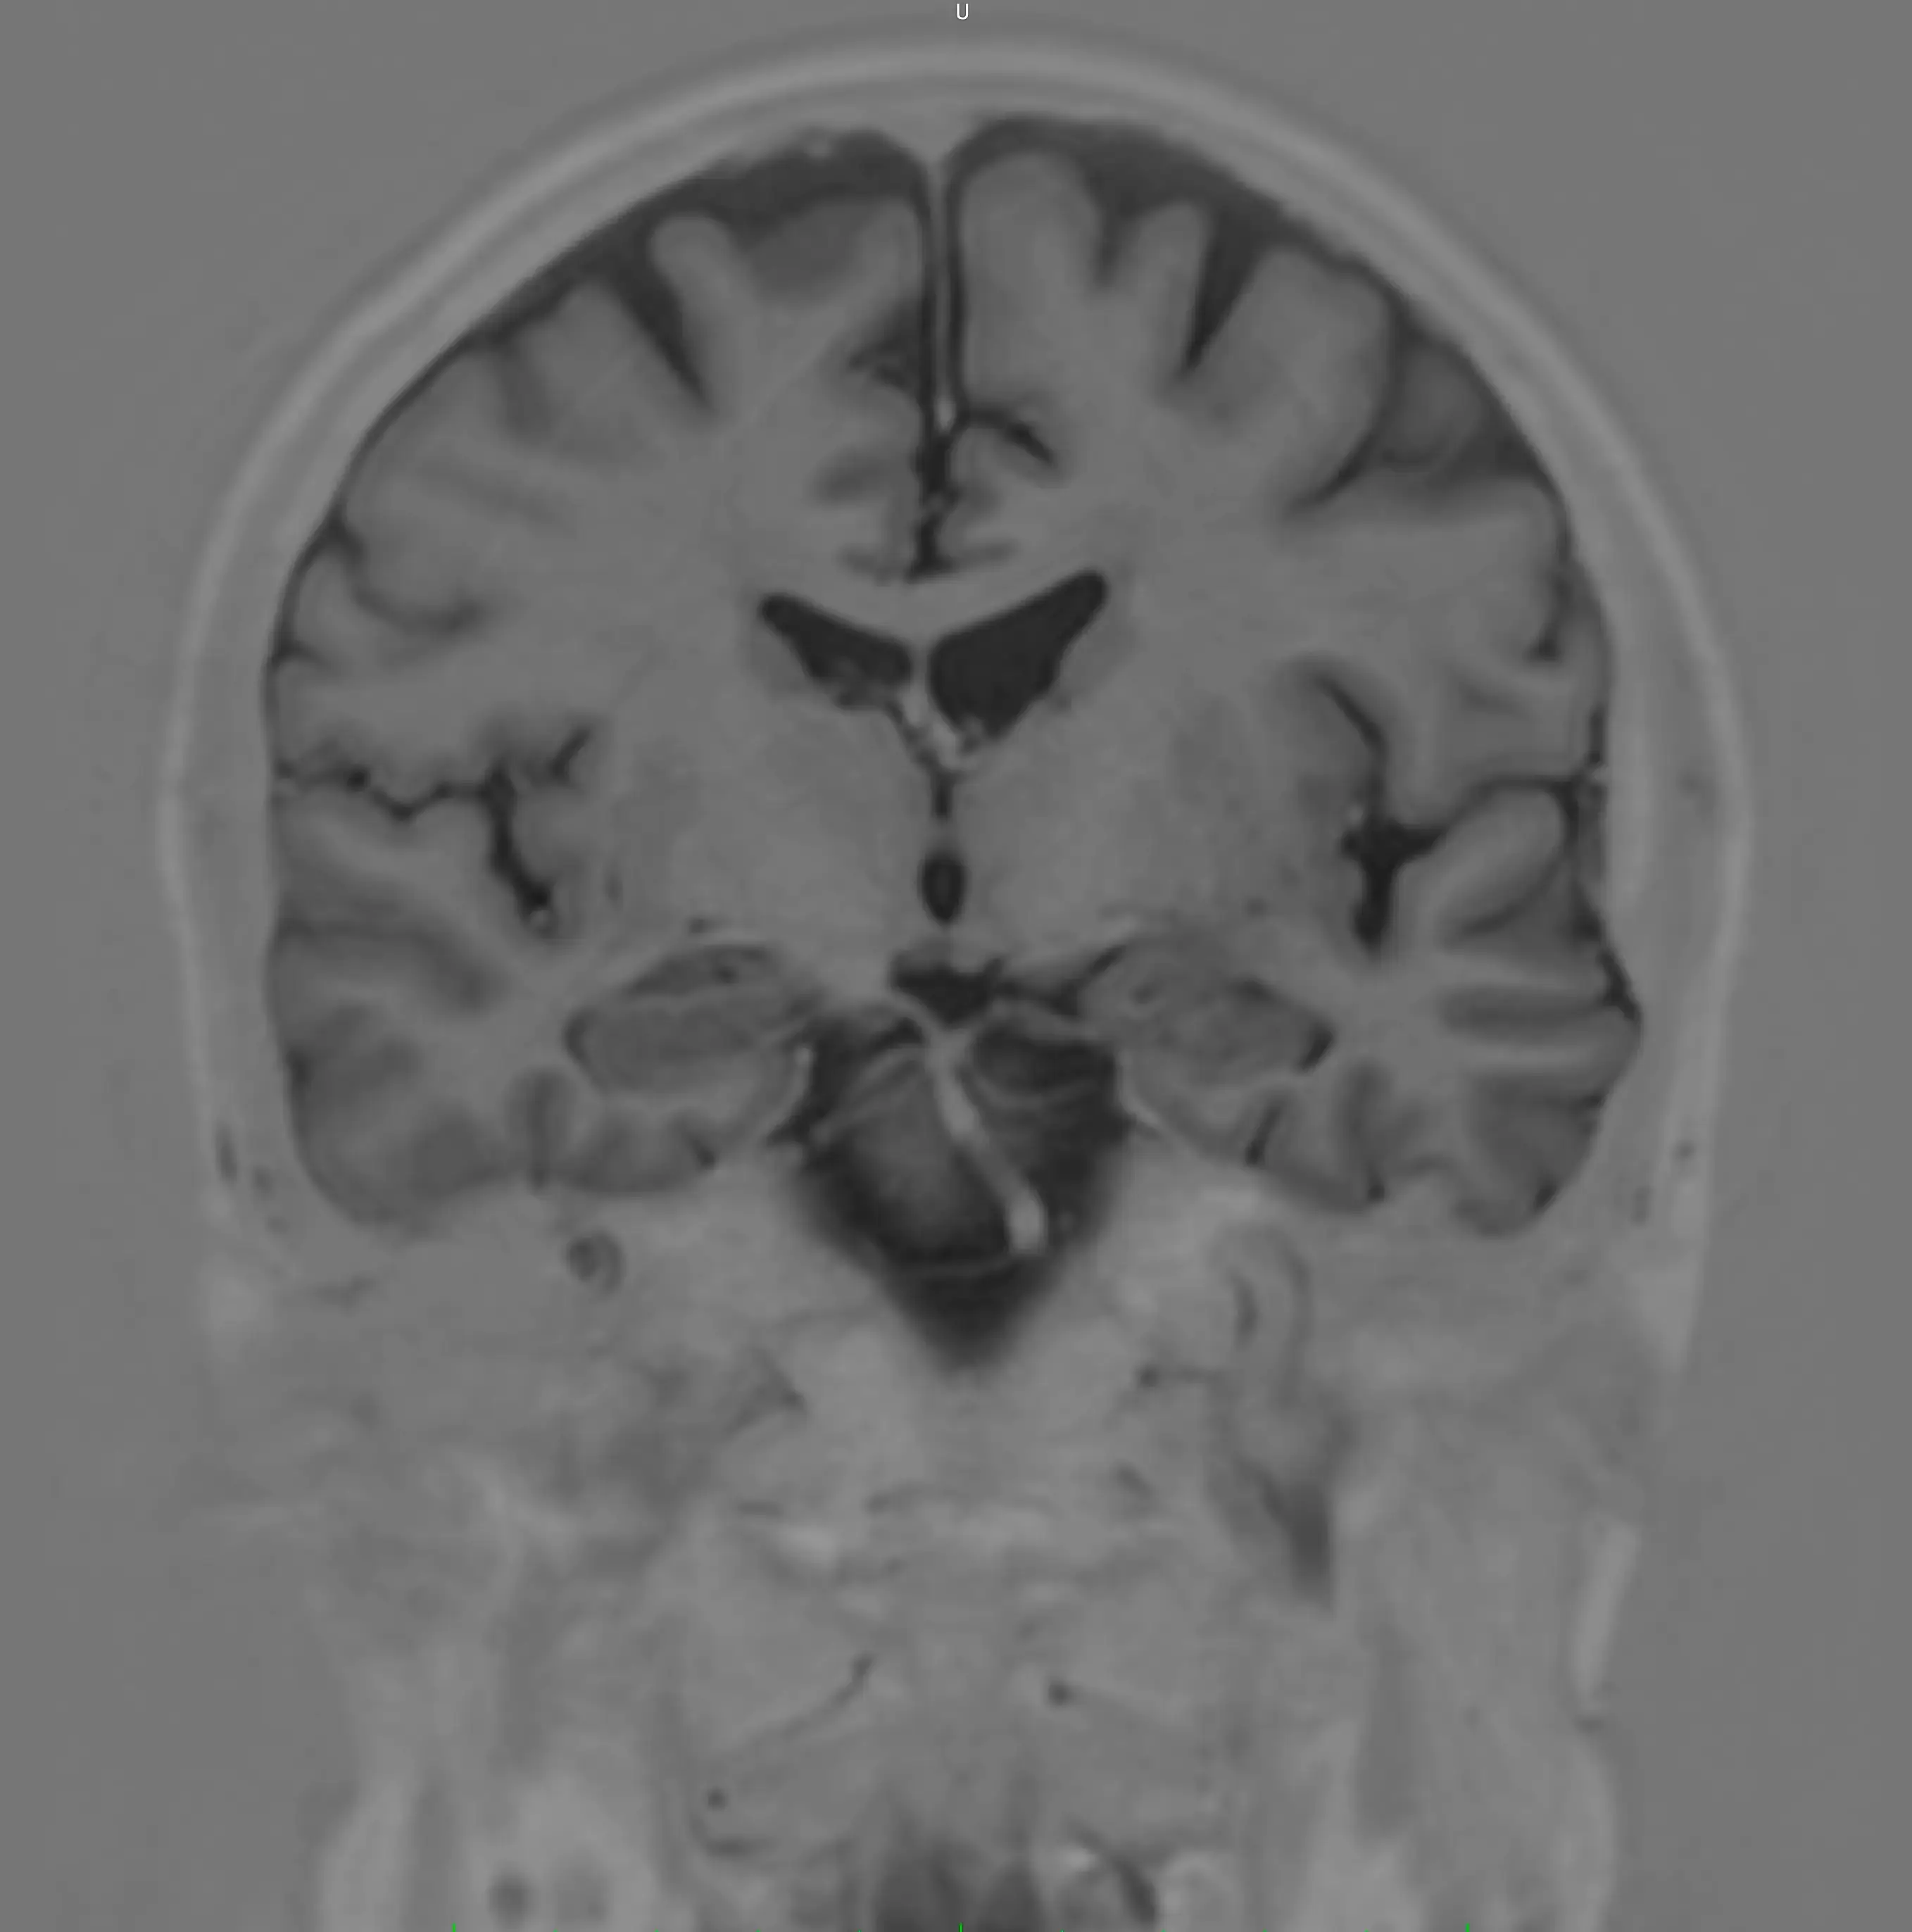

У центрі встановлено інноваційний МРТ Philips Ingenia 1.5T, оснащений технологіями штучного інтелекту (AI), що забезпечує високу точність зображень та дозволяє виявляти патології навіть на ранніх стадіях.

У центрі встановлено Philips Ingenia 1.5T — один із найсучасніших МРТ-апаратів у світі.

Наші можливості МРТ

У центрі проводяться МРТ-дослідження:

- головного мозку

Сучасні можливості МРТ дозволяють виявляти захворювання на ранніх стадіях.